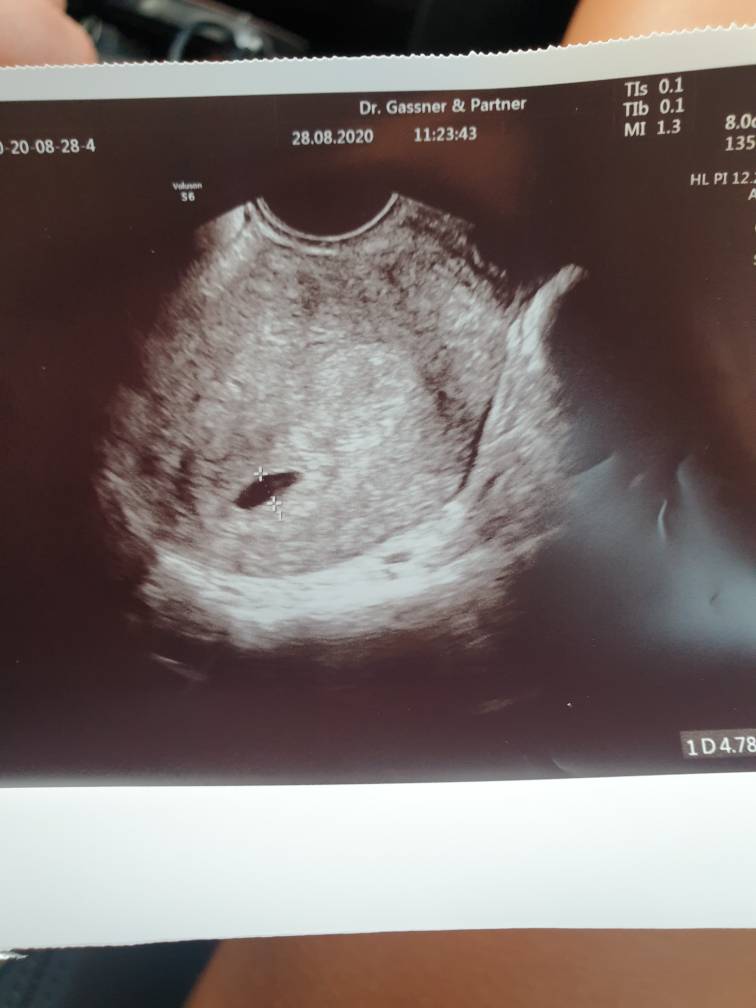

U mnie ostatnio bylo 5+4 jest pecherzyk kolejna wizyta za tydzien zeby bylo juz serduszko. Objawow zero tylko jestem wyczulona na zapachy. U was pecherzyk w tym tyg tez tak wygladal?Zobacz załącznik 1171078

U mnie wyglądał tak, termin OM podobny, ale mi wczoraj lekarz wykreślił z karty termin OM bo nie ma nic wspólnego z ciąża 🤭 ale cyjle mam 35 dniowe. Kolejna wizyta u mnie za 3 tygodnie. A Twoja za ile? Za miesiąc??